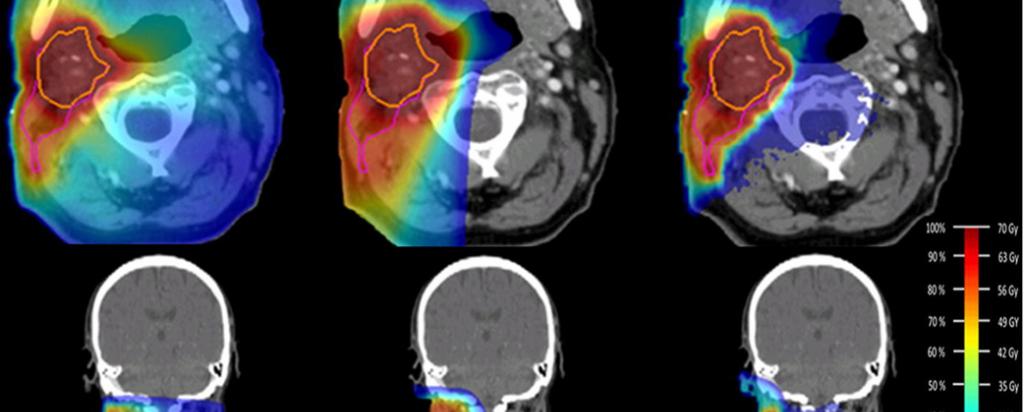

Heavy ions deliver the maximum dose at the site of the tumour, since they deposit their energy at the very end of their path through matter (known as the Bragg peak) and largely spare the surrounding healthy tissue.

“What you see and quantify in the image allows you to determine the depth at which the dose was deposited, and confirm that it conforms to the tumour site,” said Ahmed.

Heavy ion therapy is quite sensitive to spatial range uncertainties due to its very steep dose profile, research such as Ahmed's is supporting the development of new methods for direct dose estimation based on the detection of secondary fragments.